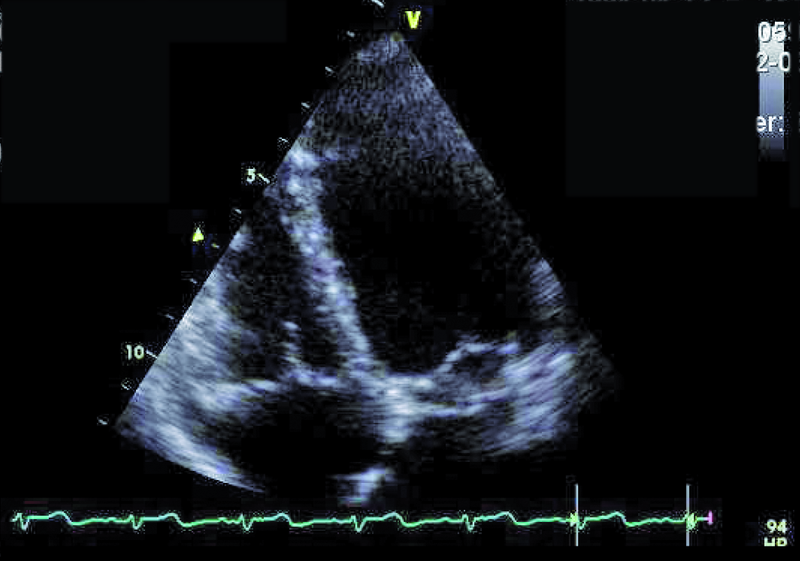

Przedstawiona chora, prawie dorosła kobieta, znajduje się w tej drugiej grupie. Jamy serca są u niej niepowiększone, a mięsień ma prawidłową grubość (ryc. 1). Rozpoznanie membrany w jamie lewego przedsionka z prawidłowym obrazem zastawki mitralnej nie nastręcza trudności. Membranę można dostrzec w wielu projekcjach (ryc. 2-4). Badanie przezprzełykowe pozwala na bardziej precyzyjne określenie średnicy otworu, która zazwyczaj waha się od kilku milimetrów do centymetra. W omawianym przypadku otwór jest duży i na podstawie samej jego wielkości można przypuszczać, że nie powoduje obstrukcji przepływu (membrana w projekcji na rycinie 4 znajduje się powyżej zastawki). Tryb doplera ciągłego (ryc. 5) także nie potwierdza zaburzeń przepływu i trudno się spodziewać, by w takiej sytuacji mogło dojść do podwyższenia ciśnienia w żyłach płucnych, włośniczkach i pniu płucnym. Średnica pnia płucnego (21 mm, ryc. 6) jest dowodem na panujące w nim niskie ciśnienie (nie zarejestrowano w badaniu fali zwrotnej trójdzielnej). Serce trójprzedsionkowe z niskim gradientem śródprzedsionkowym przy braku dodatkowych nieprawidłowości (np. przecieku międzyprzedsionkowego lewo-prawego bądź prawo-lewego – zależnie, z jaką jamą ubytek się komunikuje) nie wymaga leczenia operacyjnego. Pacjentka wymaga dalszej kontroli, ponieważ po wielu latach choroby mogą pojawić się napadowe lub utrwalone nadkomorowe zaburzenia rytmu serca, będące wyrazem zmiany geometrii przedsionka.